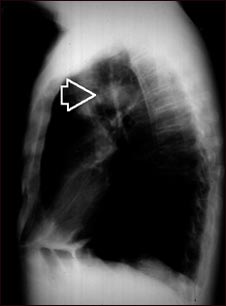

Masa pulmonar - Vista lateral de la radiografía de tórax

La parte superior del pulmón de este individuo presenta una masa. Aunque la causa puede sospecharse de acuerdo con los antecedentes de esta persona, existen muchas enfermedades que pueden producir lesiones pulmonares.